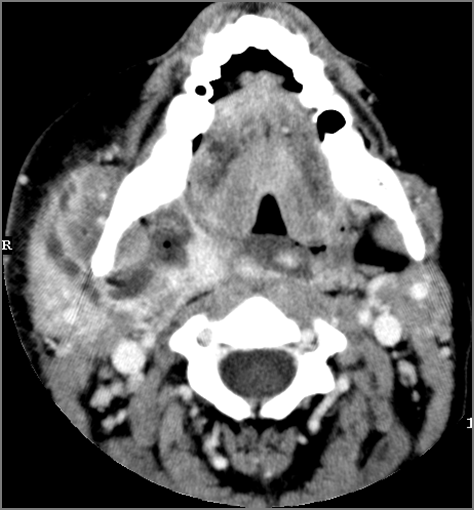

Oropharynx and Nasopharynx

There is excessive enhancement or thickening of the mucosa or hypertrophy of the pharyngeal, palatine or lingual tonsillar tissue or the lymphoid tissue along the glossotonsillar sulci and posterior pharyngeal wall. [Yes/No]

There is an abscess relatively centrally within the lymphoid tissue of the palatine tonsil. [Yes/No]

There is evidence of a developing abscess at the periphery of the lymphoid tissue of the palatine tonsil within the potential peritonsillar space. [Yes/No]

There is edema or abscess within the fat of the adjacent parapharyngeal and retropharyngeal space. [Yes/No]